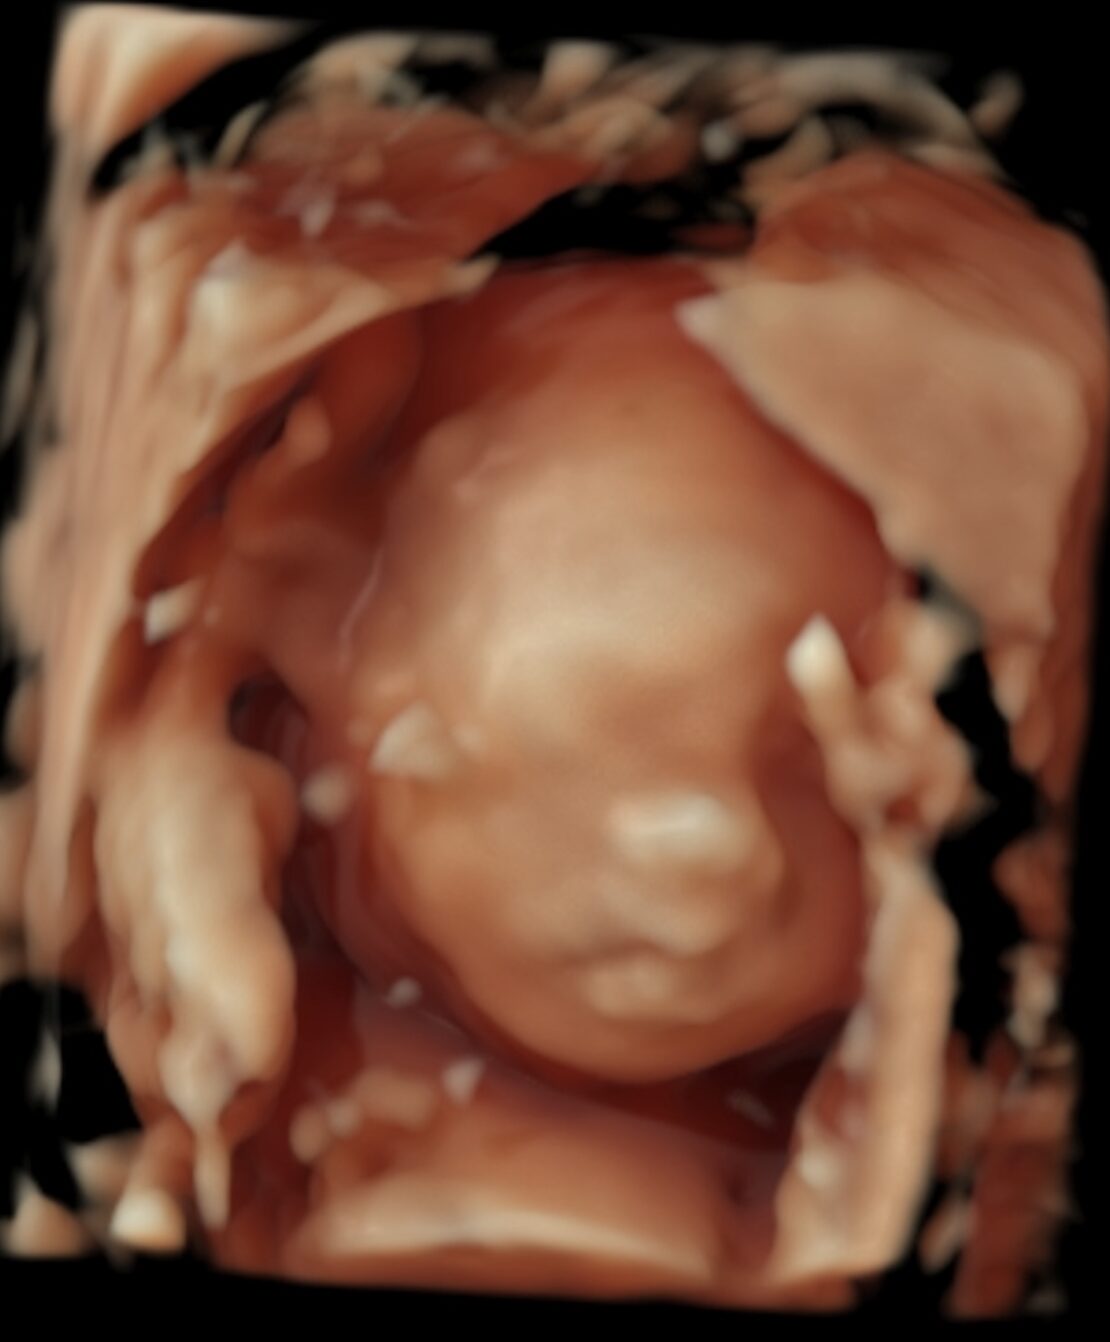

当院開院にあたっては胎児ドックで病気の診断をしっかり行うことに加えて妊婦健診でも他のクリニックでの経験などを元に少しでも妊婦さんたちに満足してもらえるクリニックを目指そうとスタッフ一同邁進してまいりました。

当院では胎児ドックでの精密超音波検査に加えて血清マーカー検査、NIPT(新型出生前検査)、絨毛染色体検査、羊水染色体検査、マイクロアレイ、エクソーム解析など出生前に行える検査はほぼ全て可能な施設となっています。

#胎児エコー #胎児ドック #NT #NIPT #新型出生前診断検査 #首のむくみ #天王寺 #阿倍野 #大阪 #よりおか胎児クリニック #あべのハルカス #ハルカス #産婦人科 #3D4D #SNPマイクロアレイ #エクソーム解析 #絨毛検査 #羊水検査